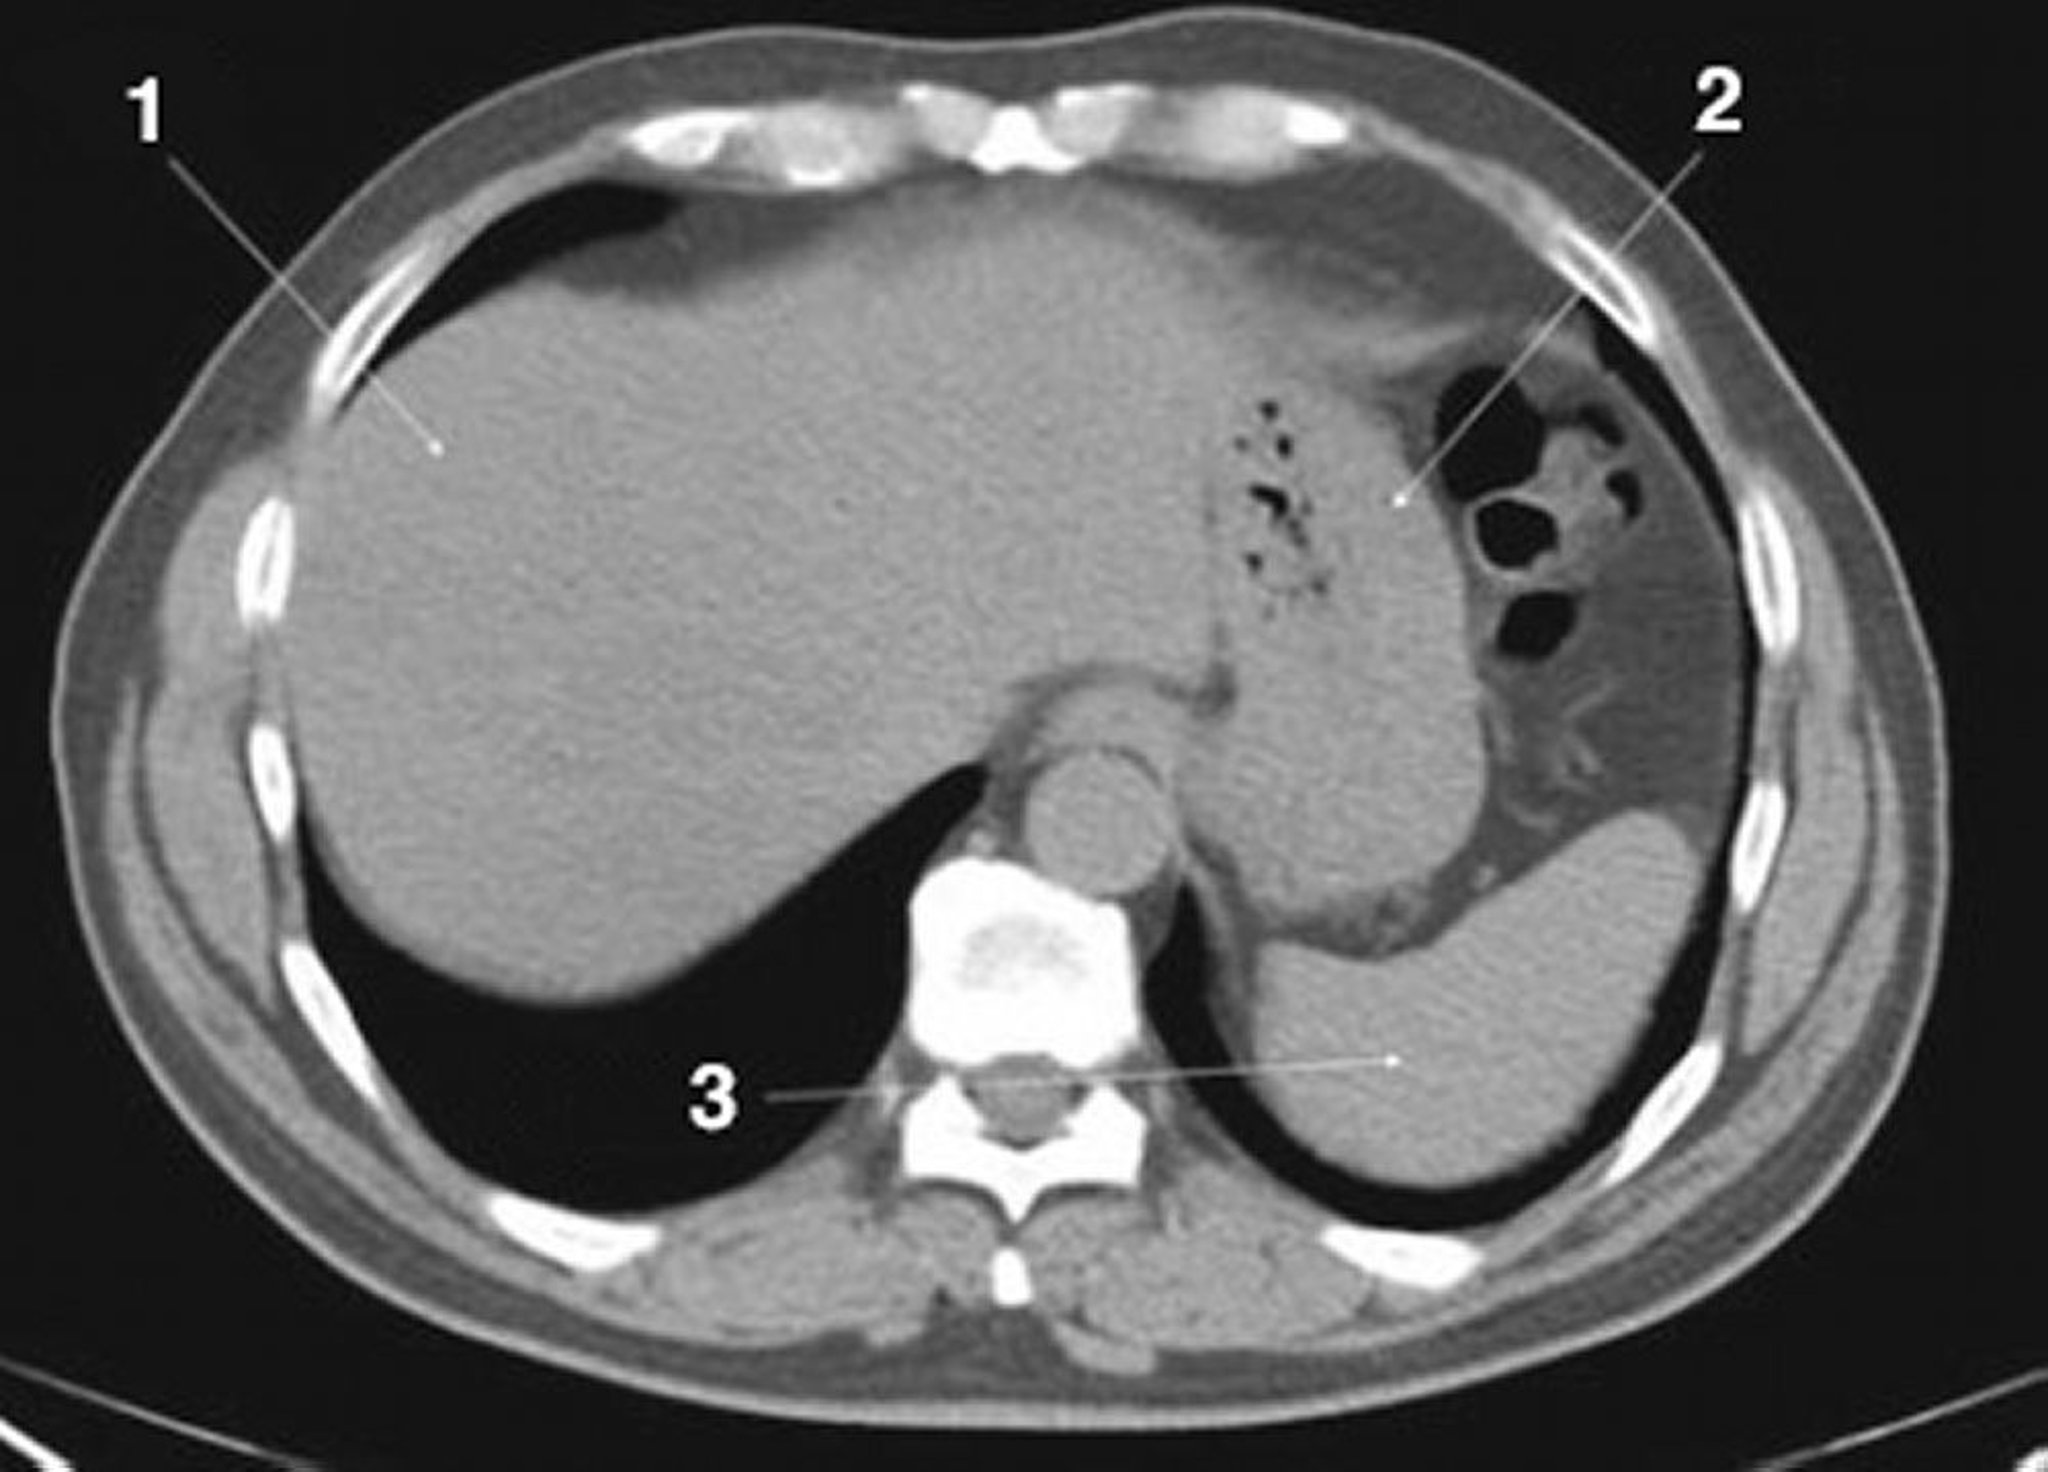

TC senza contrasto dell'addome e della pelvi che mostra un'anatomia normale (Slide 3)

1 = fegato; 2 = stomaco; 3 = milza.